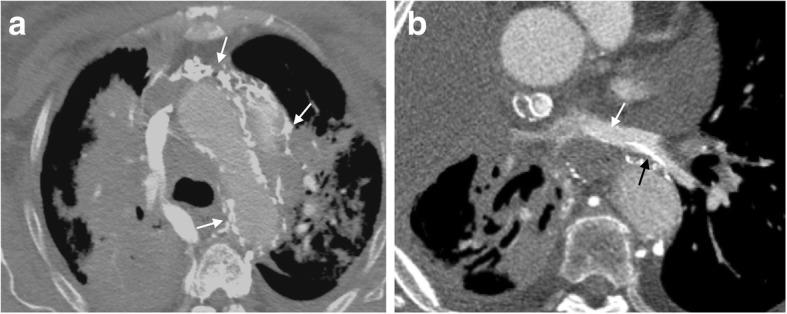

In the healthy patient, blood returns to the heart via classic venous pathways. Obstruction of any one of these pathways will result in blood flow finding new collateral pathways to return to the heart. Although significant anatomic variation exists and multiple collateral vessels are often present in the same patient, it is a general rule that the collateral pathways formed are a function of the site of venous blockage. Therefore, knowledge of typical collateral vessel systems can provide insight in localizing venous obstruction and characterizing its severity and chronicity. In addition, knowledge of collateral anatomy can be essential in interventional procedural and/or surgical planning, especially when placing catheters in patients with venous blockage. In this pictorial review, we provide a systematic approach to understanding collateral pathways in patients with venous obstruction in the upper body.

在健康患者中,血液通过经典静脉途径回流至心脏。这些途径中任何一条受阻都会导致血流寻找新的侧支途径回流至心脏。尽管存在显著的解剖变异,且同一患者体内常存在多条侧支血管,但一般规律是,形成的侧支途径取决于静脉阻塞的部位。因此,了解典型的侧支血管系统有助于定位静脉阻塞并判断其严重程度和慢性化情况。此外,了解侧支解剖结构对于介入操作和/或手术规划至关重要,尤其是在为静脉阻塞患者放置导管时。在本图文综述中,我们提供了一种系统方法,用于理解上身静脉阻塞患者的侧支途径。